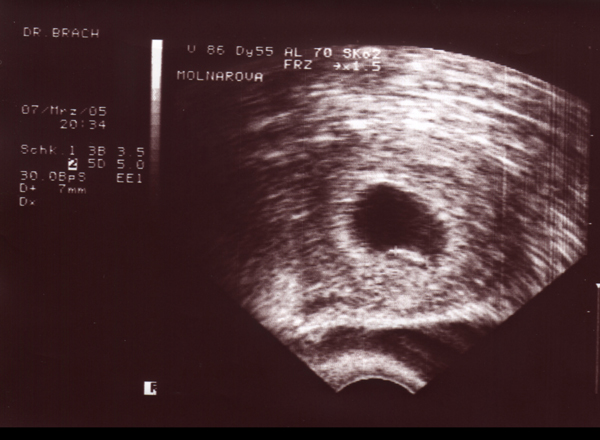

22.04.05 - 07. Woche - 0,7cm

09.05.05 - 10. Woche - 2,0cm